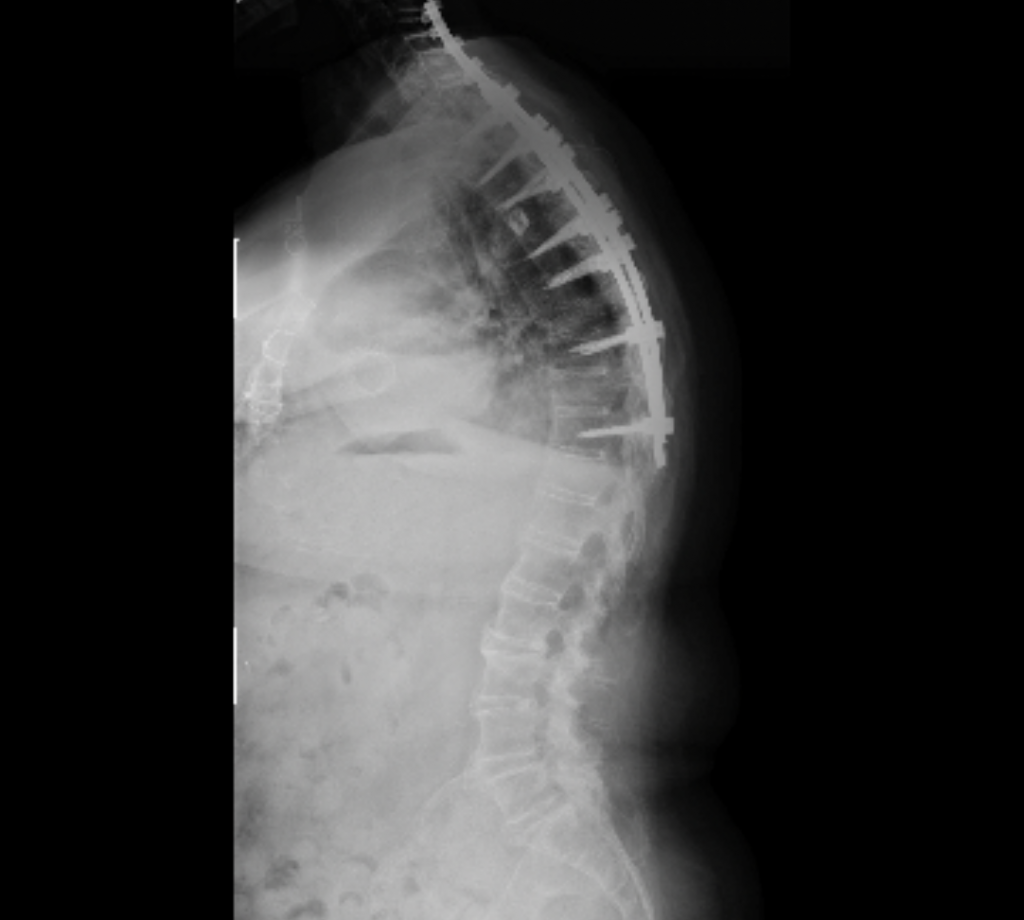

When I met Dr. Kim, he explained everything in terms I could understand, gave me time to process, and answered all my questions. I continued seeing him as a DISH patient until February 2023, when I suffered a thoracic fracture, followed by a cervical fracture in July 2023. Both required emergency surgeries, and after discharge, I was left with cervical kyphosis and displaced hardware.

The cervical fracture caused a spinal cord injury, leaving me paralyzed in both arms for 12–18 months. My rehabilitation journey included intensive inpatient therapy, subacute rehab, home therapy, and finally outpatient therapy. Once I felt ready to discuss another spinal surgery, I returned to Dr. Kim.

After reviewing my x-rays, CT, and MRI, Dr. Kim recommended a Pedicle Subtraction Osteotomy (PSO). During surgical clearance, an abnormal EKG required cardiac evaluation. I had a congenital heart defect repaired in 2014 with valve replacement, and my cardiology team determined the valve needed repair before spinal surgery. This caused significant delays, as insurance denied authorization three times before approving a valve-in-valve repair in November 2024.

Finally, I was cleared for the PSO with Dr. Kim. Throughout this entire process, Dr. Kim and his team were incredible - supportive, patient, and reassuring. Today, my posture has improved significantly, and I can hold my head high, smile, and be thankful for the outstanding care I received.